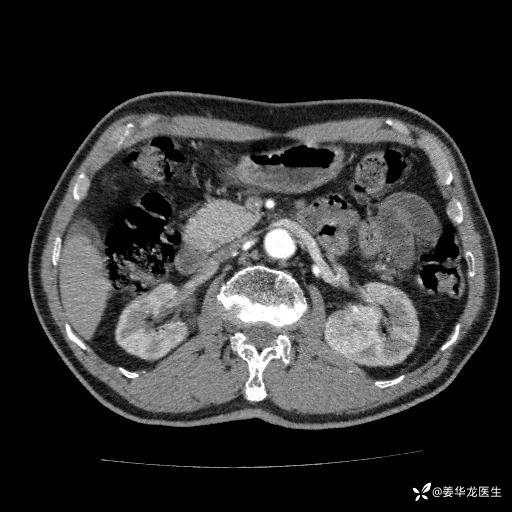

左肾中心型肾门部肿瘤39mm×34mm×36mm,右肾GFR25ml/min,部分切还是全切?

患者75岁老年男性,体重50kg,无高血压、肾病、糖尿病等基础病,检查发现左肾中心型肾门部肿瘤,右肾GFR只有25ml,无肉眼血尿,无镜下血尿。入院验血常规检查均正常,包括肾功能,肌酐102.7umol/L.

二、左肾肿瘤与左肾集合系、左肾动静脉关系密切,左肾部分切除术可行吗?成功率有多大?成功部分切后,肾功能还有多少?